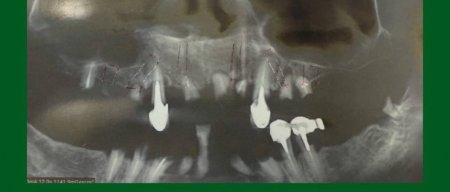

Дентальні протези – один з найефективніших і тривалих методів лікування. Імпланти – це штучно створені коренеподібні штифти з титану, які імплантуються в щелепу і служать кріпленням для зубних протезів. Цей метал максимально схожий за характеристиками на кісткову тканину і може служити до 20 років. Вимоги до коронок не менше високі, ніж до штифтів. Вони повинні бути міцними і не розколюватися при вживанні твердої їжі. Коронки робляться з металокераміки, а також діоксиду цирконію. В якості тимчасових коронок на штифт може вдягатися Металопластмаса.

- Самостійно вибрати зубний імплант — це нерозв’язне завдання для неспеціаліста. Підбір імплантаційної системи слід довірити досвідченому лікарю, який проведе 3D діагностику і запропонує відповідні варіанти реконструкції посмішки.

Ключ до успішної імплантації — точна діагностика. В арсеналі “ДентЛюкс” є один із найкращих КТ-апаратів в Україні— PLANMECA VISO G7.

Завдяки 3D-діагностиці імпланти встановлюються з ідеальною точністю. Результат — безпечно, комфортно та надовго.